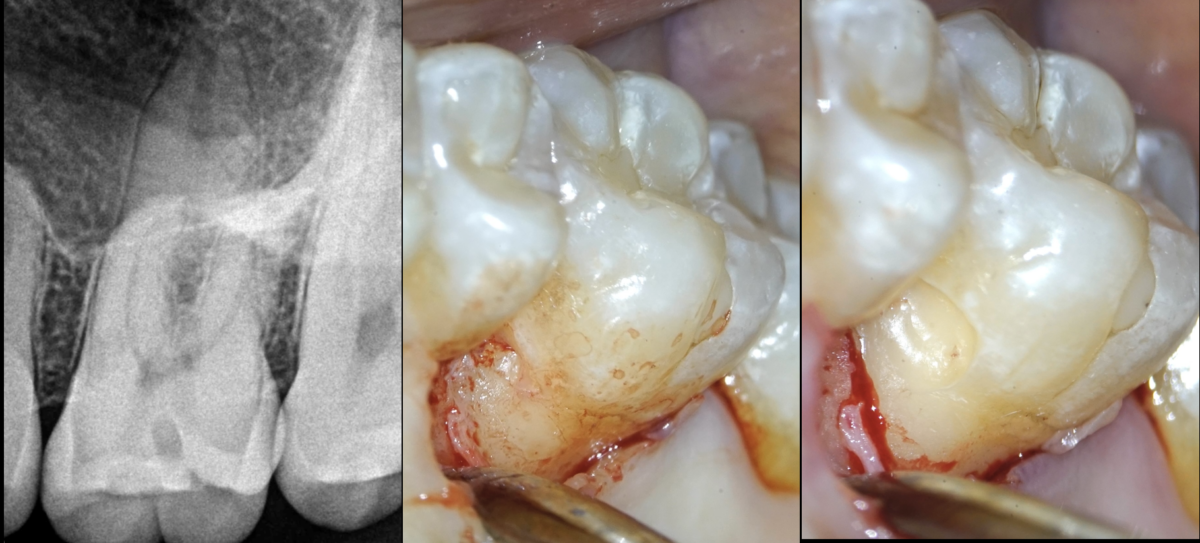

🔍Dent n°26.

Pulpe normale. Os péri apical normal.

Résorption radiculaire externe, cervicale, inflammatoire, côté palato-mésial.

➡️ Microchirurgie de la résorption sans traitement canalaire.

💡 𝐄𝐫𝐠𝐨𝐧𝐨𝐦𝐢𝐞 𝐝𝐢𝐟𝐟𝐞́𝐫𝐞𝐧𝐭𝐞 𝐝𝐞 𝐜𝐞 𝐪𝐮𝐞 𝐧𝐨𝐮𝐬 𝐚𝐯𝐨𝐧𝐬 𝐥’𝐡𝐚𝐛𝐢𝐭𝐮𝐝𝐞 𝐝𝐞 𝐟𝐚𝐢𝐫𝐞 𝐞𝐧 𝐯𝐞𝐬𝐭𝐢𝐛𝐮𝐥𝐚𝐢𝐫𝐞 : 𝐭𝐞̂𝐭𝐞 𝐞𝐧 𝐡𝐲𝐩𝐞𝐫𝐭𝐞𝐧𝐬𝐢𝐨𝐧 𝐞𝐭 𝐨𝐫𝐢𝐞𝐧𝐭𝐞́𝐞 𝐚̀ 𝐠𝐚𝐮𝐜𝐡𝐞, 𝐝𝐞 𝐟𝐚𝐜̧𝐨𝐧 𝐚̀ 𝐚𝐯𝐨𝐢𝐫 𝐮𝐧𝐞 𝐯𝐢𝐬𝐢𝐨𝐧 𝐝𝐢𝐫𝐞𝐜𝐭𝐞.